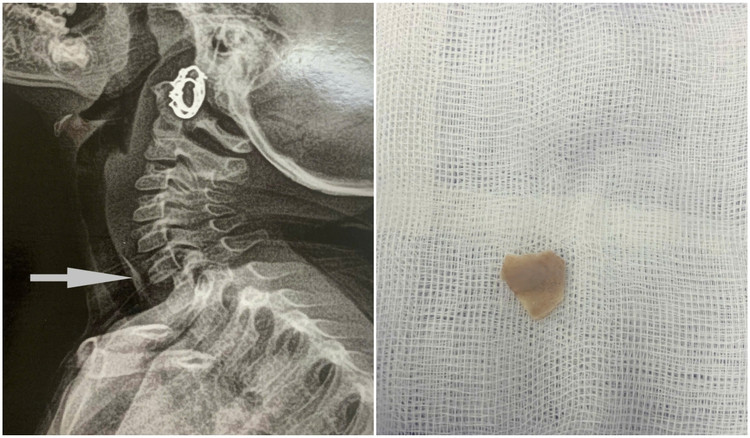

| Hình ảnh bệnh nhân M. bị hóc xương gà vùng thực quản cổ được bác sĩ nội soi lấy ra an toàn - Ảnh BVCC |

Trường hợp thứ 2 là bệnh nhân Ngô Văn M. (44 tuổi), nhập viện ngày 7/2/2025 trong tình trạng nuốt đau, nuốt nghẹn. Các bác sĩ thăm khám, chụp cắt lớp chẩn đoán bệnh nhân M. bị hóc xương gà vùng thực quản cổ ngày thứ nhất và đã được bác sĩ khoa Tai mũi họng nội soi lấy dị vật an toàn.